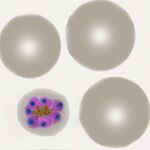

| Plasmodium ovale |

Brief summary

- rings are large and robust, with ring appearance often retained in late trophozoite stage

- Red cells are enlarged often with oval shape and may have characteristic fimbriation

- Schüffner's (James) dots seen in appropriately stained samples

- All forms tend to circulate, parasites are large but tend to be smaller than for P.vivax